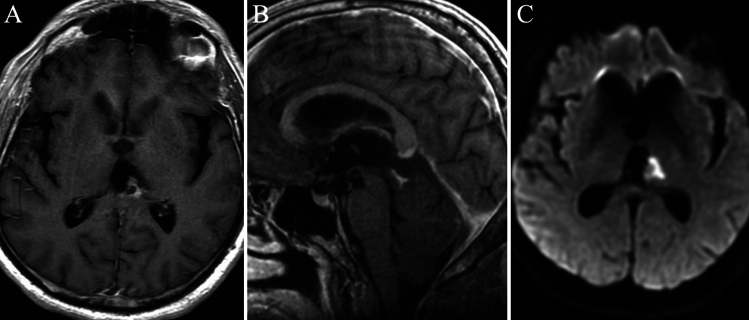

Lessons: HGAP, a distinct glioma subtype identified in 2021, presents a mix of low- and high-grade features. It shares histological traits with pilocytic astrocytoma and glioblastoma, requiring DNA methylation profiling for diagnosis. Radiologically, these lesions have a T2-FLAIR mismatch and uneven post-gadolinium enhancement. Treatment is still uncertain, although adjuvant chemoradiation therapy with temozolomide may be used. The prognosis is poor, with a 5-year survival rate of approximately 50%. For pineal region locations, the exoscope offers enhanced magnification, depth perception, and ergonomic benefits, improving surgical precision. https://thejns.org/doi/10.3171/CASE25390.